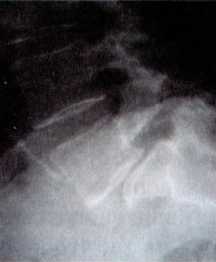

Рентгенограмма показывает смещенный позвонок (спондилолистез).

От обычного рентгена (правильнее сказать рентгеновского исследования) можно получить довольно много информации при травме позвоночника, сколиозе или смещении позвонков — спондилолистезе. Впрочем, и у пациента с патологией межпозвонковых дисков можно найти или исключить косвенные признаки грыжи. Рентгенография — метод недорогой, доступен в любой поликлинике и с него начинается обследование больного с патологией позвоночника. Вместе с тем, полноценного диагноза рентгенография не дает. Также и метод рентгенокомпьютерной томографии (РКТ) я считаю недостаточно информативным. По рентгенокомпьютерной томограмме хорошо определяется характер перелома позвонка, расположение отломков, наличие гемангиомы. А при метастазе злокачественной опухоли на РКТ четко выявляется поражение костной ткани. Но достоверно увидеть наличие и точное расположение грыжи или опухоли спинного мозга позволяет только магниторезонансная томография, выполненная на современном, так называемом высокопольном томографе. Не вдаваясь в детали, скажу — речь идет об аппарате с достаточно мощным магнитным полем (1–1,5 тесла).